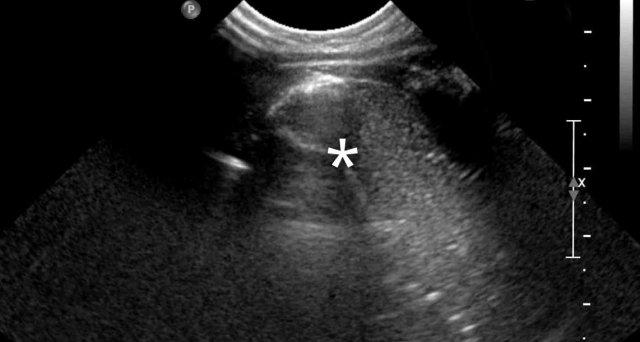

Hình ảnh

Trẻ sơ sinh đủ tháng với triệu chứng khó thở.

Mờ một phần vùng phổi trên bên trái.

Các quai ruột được nhìn thấy trong lồng ngực trái (mũi tên).

Sự dịch chuyển của các cấu trúc đường giữa được thể hiện qua sự lệch của ống thông dạ dày (đầu mũi tên)

Siêu âm cho thấy nhu động ruột trong các cấu trúc chứa khí và dịch, xác nhận thoát vị cơ hoành lớn.